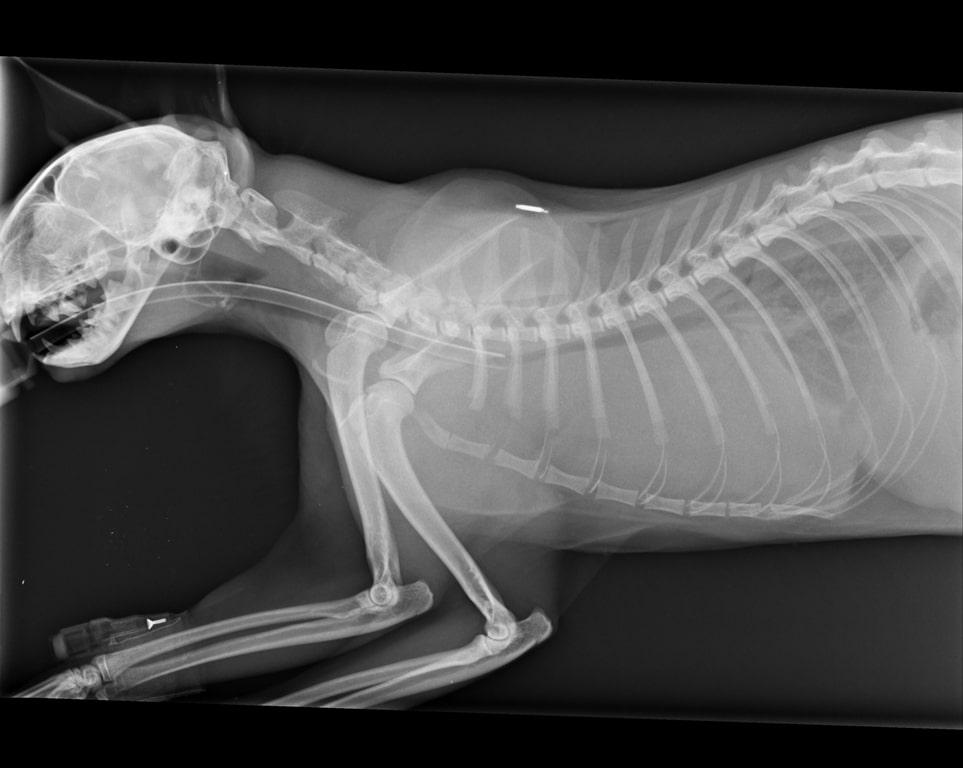

Рентген кошки

Рентген котикам назначают в разных случаях, он может быть как экстренным, так и плановым. Исследование помогает диагностировать:

- Травмы конечностей и черепа.

- Наличие инородных предметов в организме.

- Повреждение грудной клетки.

- Воспаление легких.

- Беременность и расположение котят в матке.

- Патологии челюстей.

- Аномалии сердца и легких.

- Образовавшиеся метастазы и другие новообразования.

Как подготовить питомца к рентгенографии?

Кошки при перевозке всегда испытывают стресс, поэтому на рентгенографию они могут прибыть очень встревоженными. В таком случае вы можете воспользоваться препаратом Кот Баюн , он отлично оказывает слабое успокаивающее и седативное воздействие.

Если вы живете в крупном городе, то можете вызвать врача с мобильным аппаратом для рентгенографии.

Как проходит процедура?

Котики не способны спокойно сидеть в определенной позе, а тем более в незнакомом помещении. Поэтому рентгеновский снимок помогают делать несколько специалистов. Они фиксируют кошку в нужной позе, в этом случае снимок получается качественным. И тогда на нем можно будет найти патологии или удостовериться в том, что ваша кошка полностью здорова.

Многих владельцев кошек интересует такой вопрос: представляет ли опасность рентген для кошек? В настоящее время используются только качественные аппараты, которые соответствуют регламентам всемирного здравоохранения. Поэтому процедура рентгенографии не причинит вреда вашему любимчику. Единственное, что хочется отметить, вы должны понимать, что излучение в любом случае не полезно, и несколько раз в месяц снимков не нужно делать.